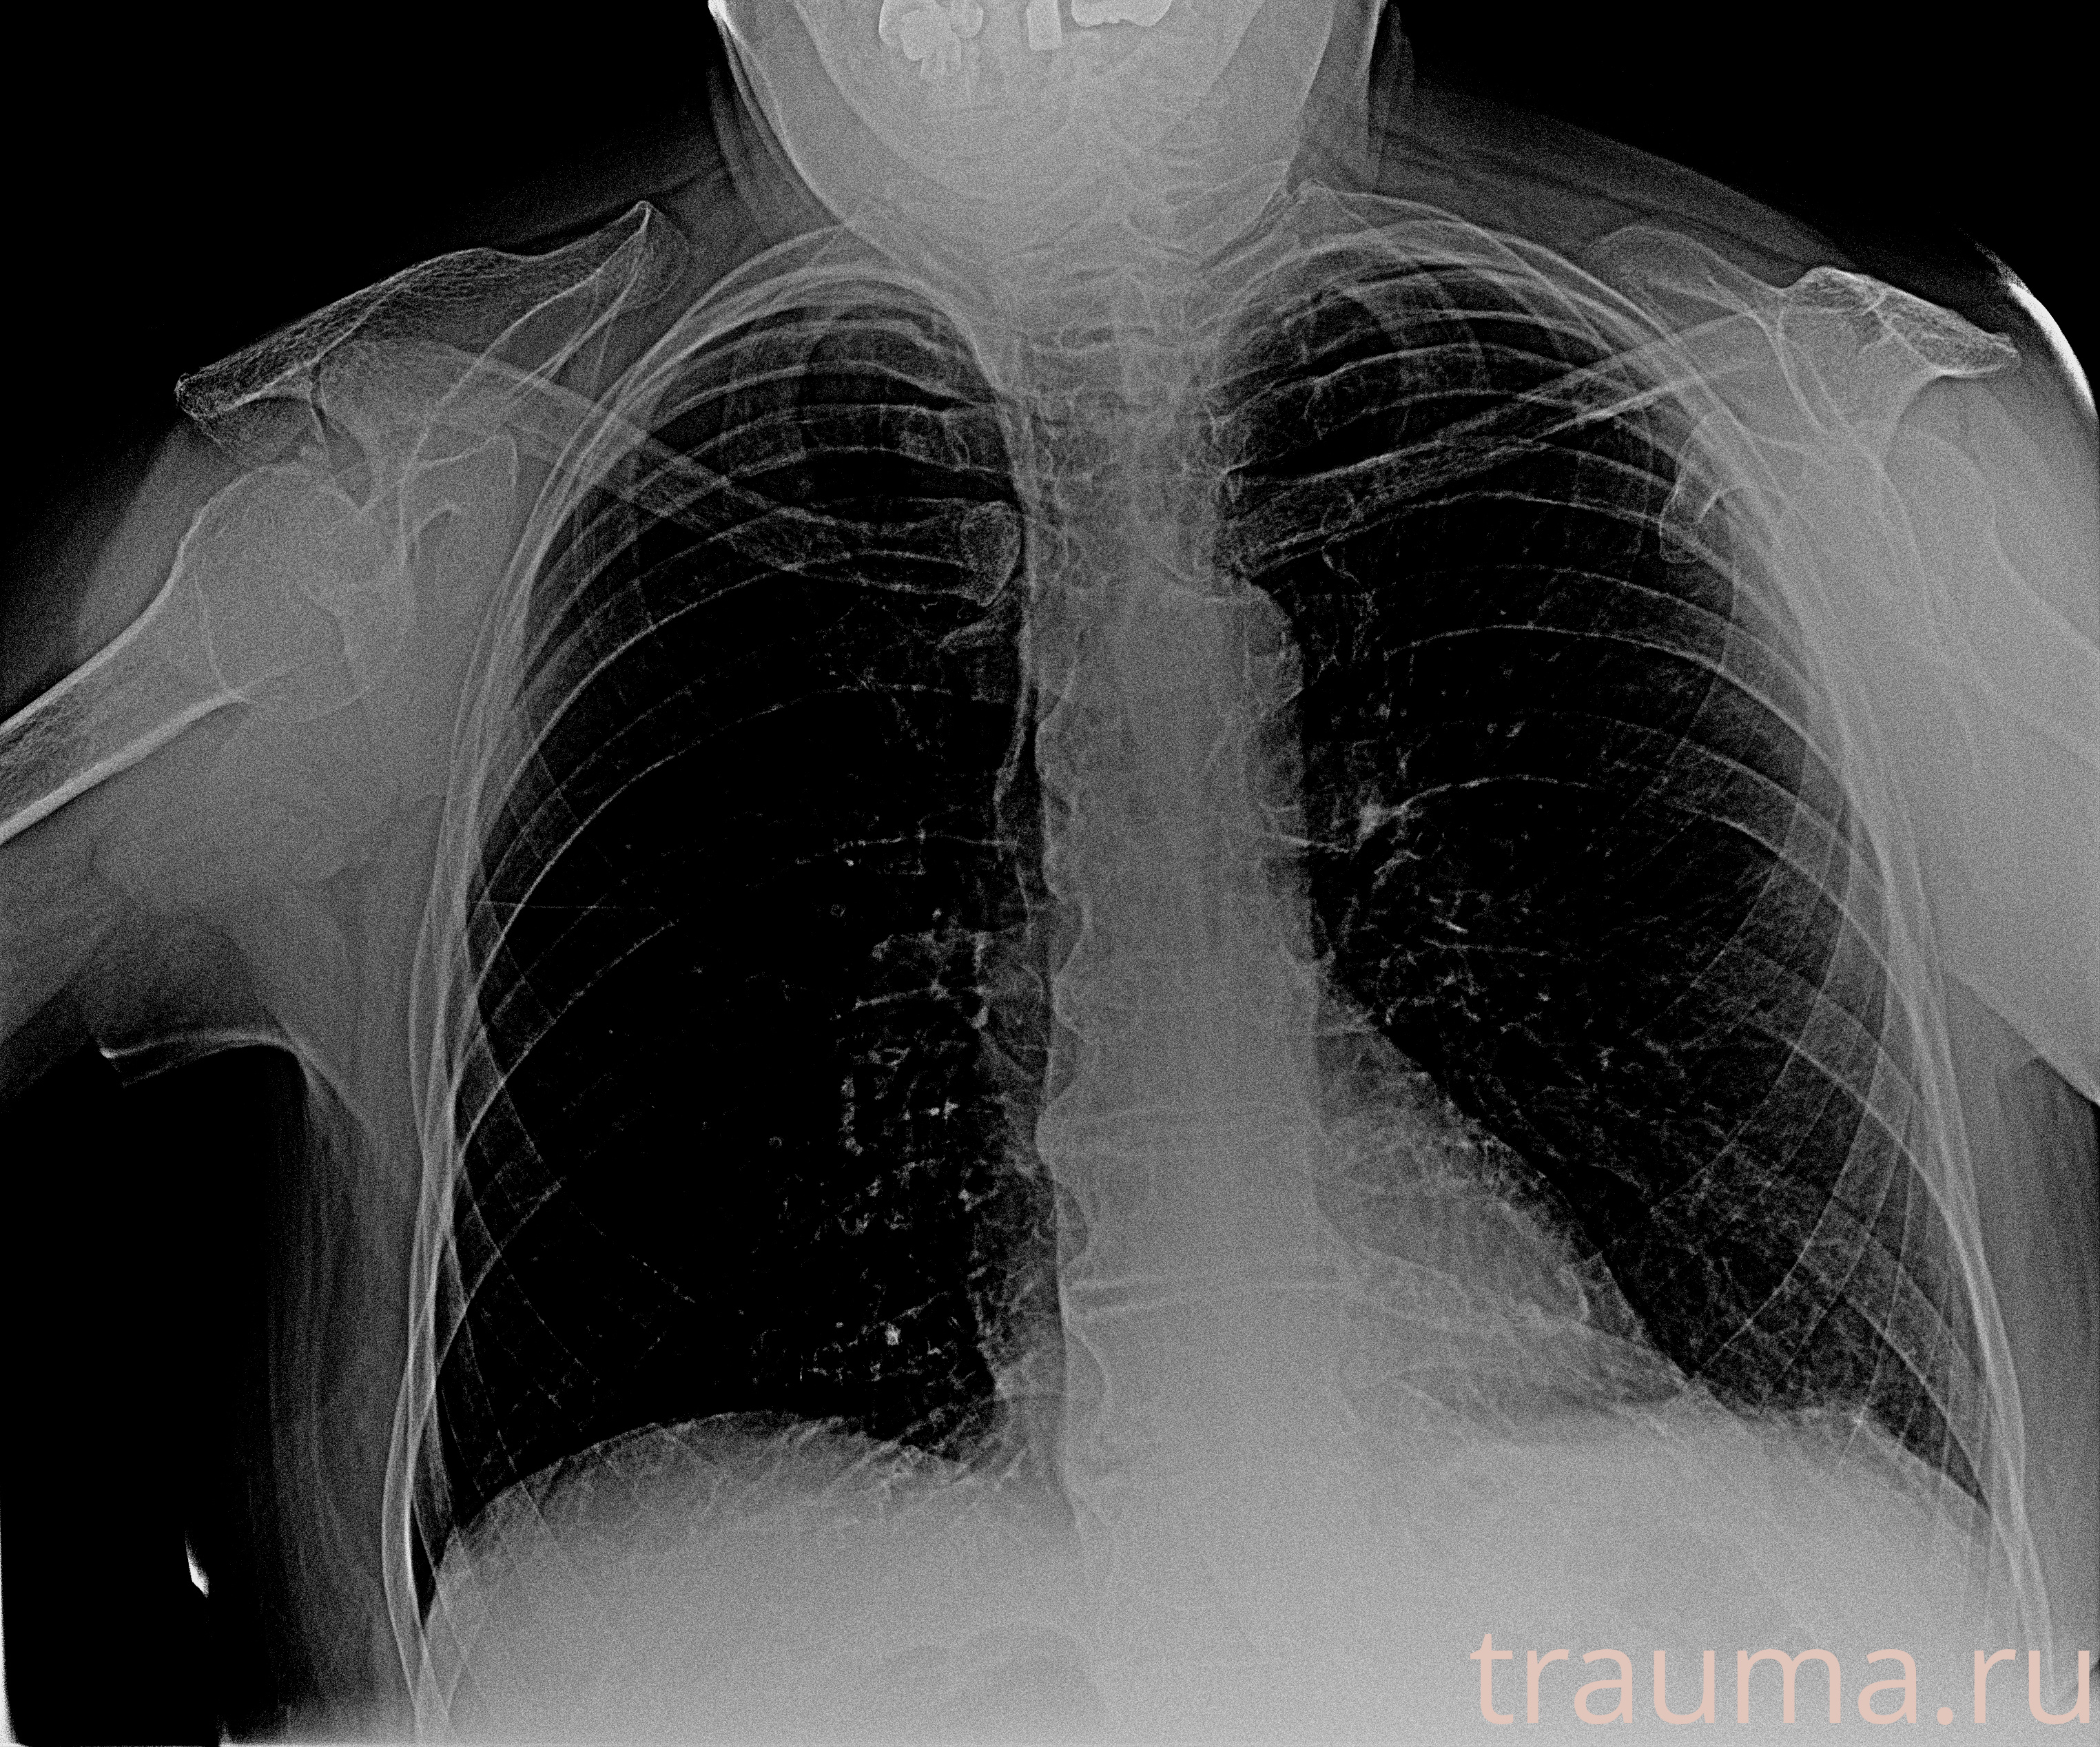

Рентгенограммы

Рентген на дому: по вашему адресу приезжает врач-рентгенолог, травматолог-ортопед с мобильным рентгеновским аппаратом, проводит диагностику травмы или заболевания, делает необходимые рентгенограммы, дает рекомендации по дальнейшему лечению. Получить качественные снимки в домашних условиях возможно благодаря уникальной методике, разработанной МосРентген Центром для института  Склифосовского

при переломе шейки бедра и пневмонии от компании МосРентген Центр - партнера Института имени Склифосовского